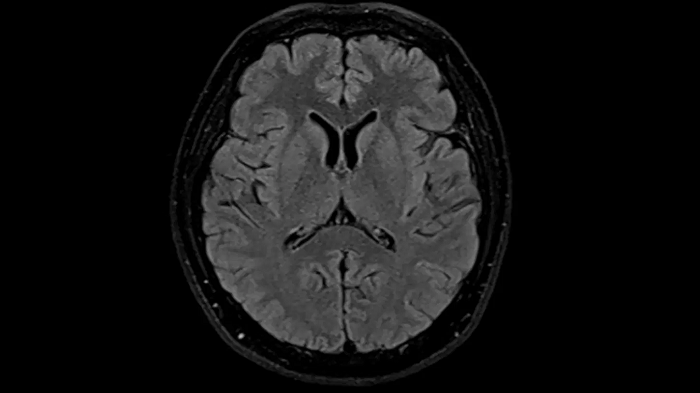

T2 TSE Dark Fluid with Deep Resolve

To produce high-resolution images, Deep Resolve, the Al-powered image reconstruction technology gets benefits from intelligent denoising and neural networks.

Deep Resolve Gain & Sharp

0.4 x 0.4 x 5.0 mm2

TA 4:32 min